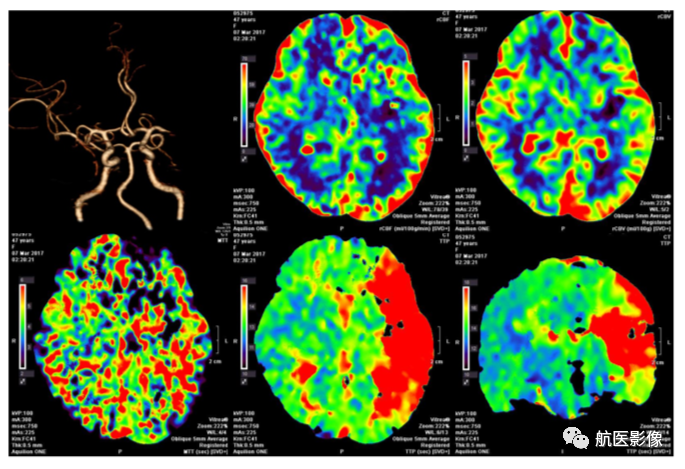

1、缺血性中风一站式CT检查:

320排CT的应用,只需注射一次造影剂即可完成所有检查(包括CT平扫、CTA、CTP),检查时间显着缩短,患者受辐射剂量显着降低。 CT扫描可以确定中风的类型; CTA可有效评估脑动脉狭窄程度及侧支血流,排除动脉瘤及血管畸形; CTP可以显示脑组织中与神经损伤相对应的局部灌注缺损区域。